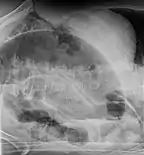

After taking a thorough history, the diagnosis of colonic volvulus is usually easily included in the differential diagnosis. Abdominal plain x-rays are commonly confirmatory for a volvulus, especially if a "bent inner tube" sign or a "coffee bean" sign are seen. These refer to the shape of the air-filled closed loop of colon which forms the volvulus. Should the diagnosis be in doubt, a barium enema may be used to demonstrate a "bird's beak" at the point where the segment of proximal bowel and distal bowel rotate to form the volvulus.

This area shows an acute and sharp tapering and looks like a bird's beak. If a perforation is suspected, barium should not be used due to its potentially lethal effects when distributed throughout the free intraperitoneal cavity. Gastrografin, which is safer, can be substituted for barium.